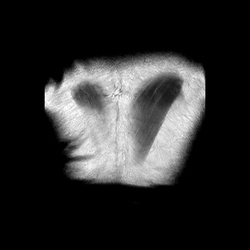

MRI_MYELO_radial_1201

6 photos